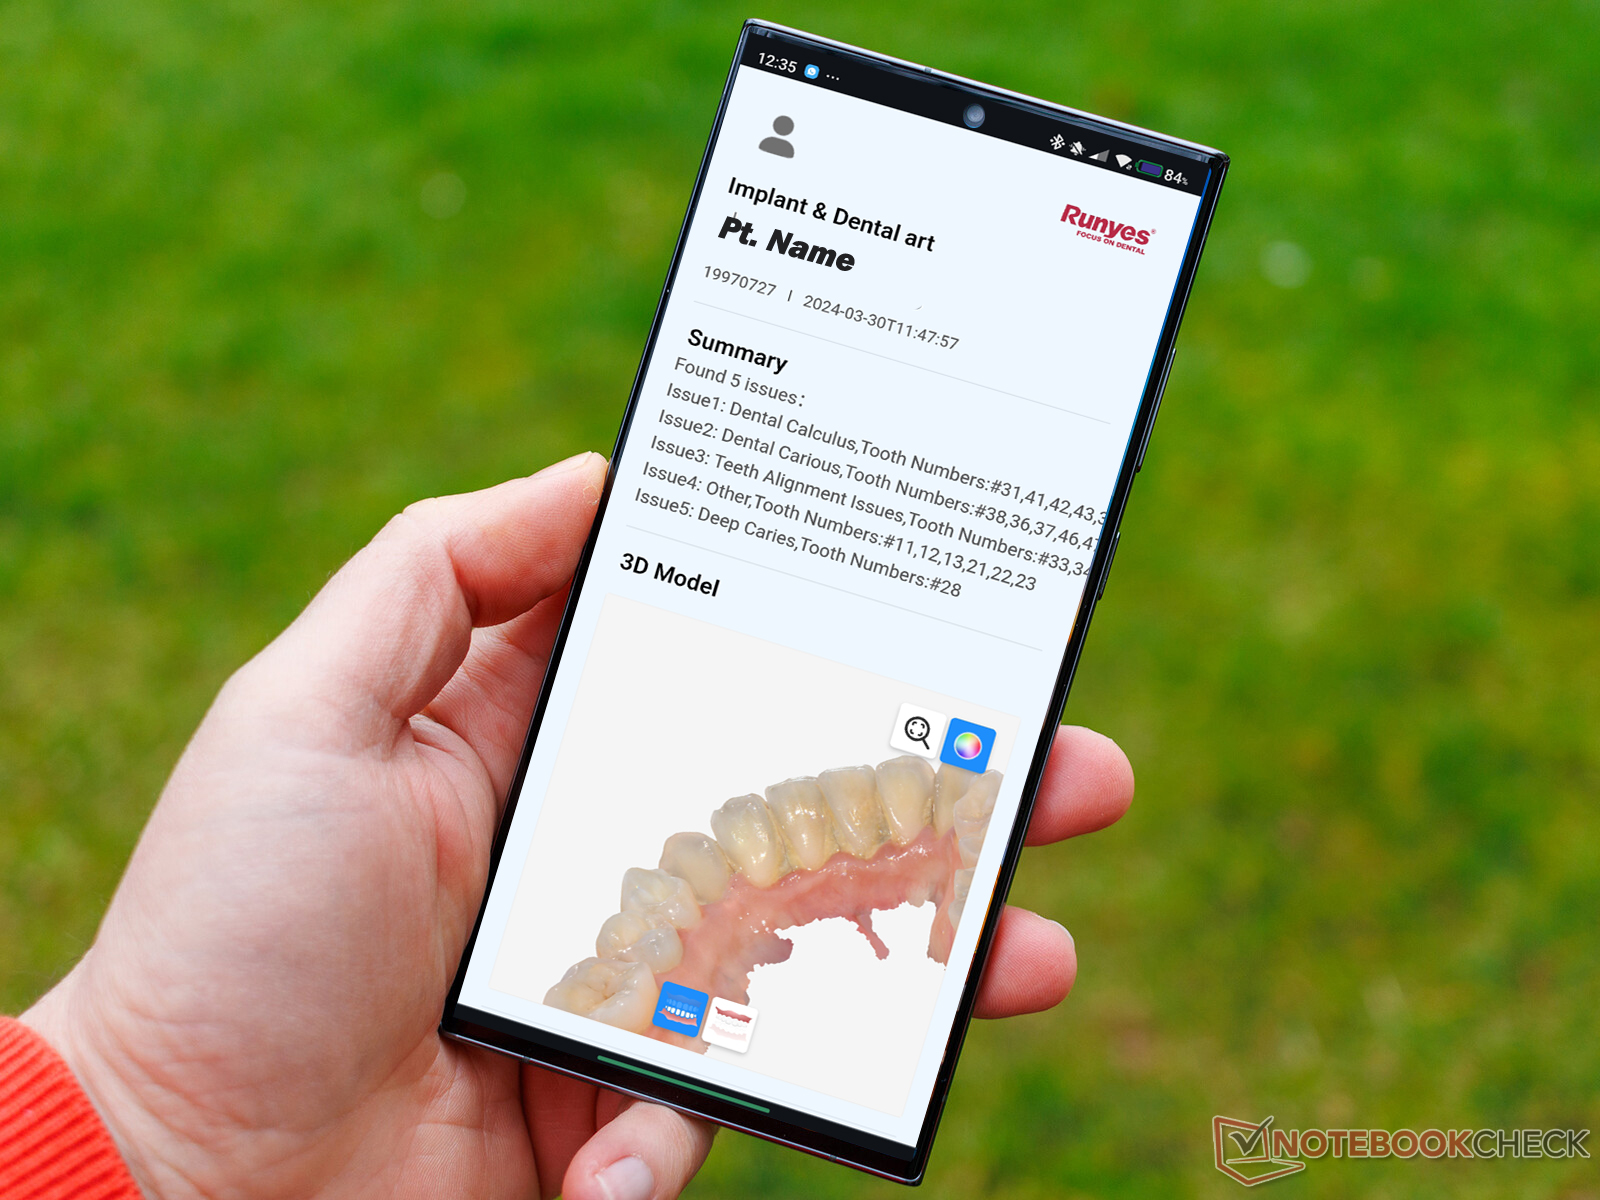

Oral Health Report

Get your mouth Scanned and Get a Health report with 3D model. Powered By Artificial Intelligence, Best to keep track of your Oral Health status. You can view it on any device Computer, tablets and cell phones (android, iOS or any other)